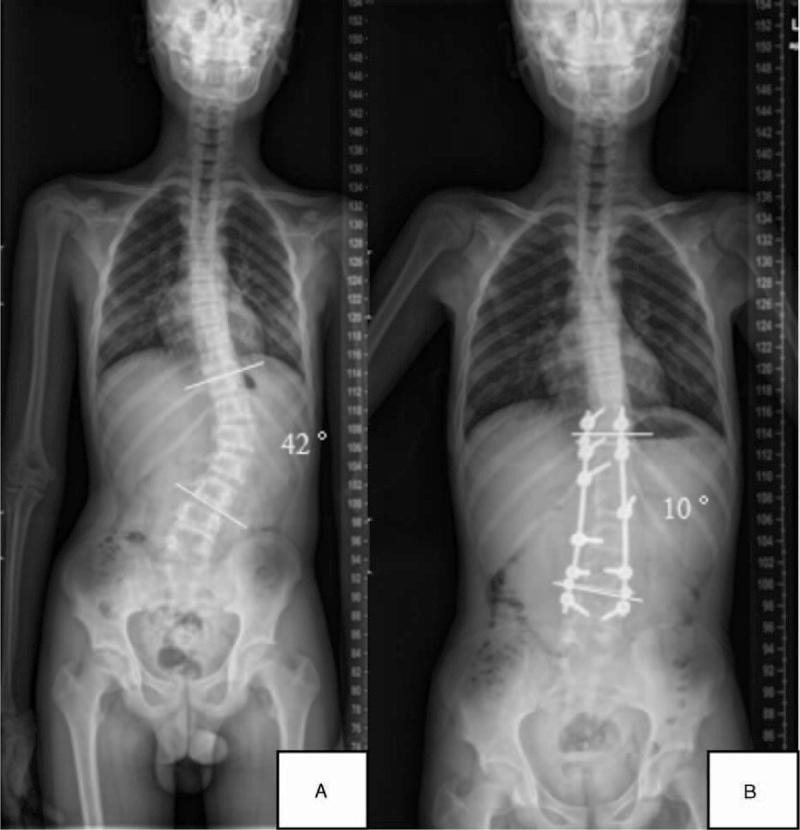

The primary aim was to compare postoperative radiographic outcomes between sexes among adolescent idiopathic scoliosis (AIS) patients. A total of 162 AIS patients (42 males and 120 females) undergoing pedicle screw instrumentation and posterior fusion were included. Coronal and sagittal curves and flexibilities were measured and calculated. The postoperative correction rate (CR), fulcrum bending correction index (FBCI), and Cincinnati correction index were evaluated to compare the surgical benefits between sexes.Males were older (16.79 vs 14.79 years, respectively; P < 0.01) and had stiffer curves than females (lateral bending flexibility percentage: 47.77 vs 52.57, respectively, P = 0.21; traction flexibility percentage: 35.48 vs 36.98, respectively, P = 0.98; fulcrum bending flexibility percentage: 56.13 vs 66.57, respectively, P < 0.05). Males and females exhibited similar Lenke classification schemes (P = 0.72), but had different Risser signs (P < 0.01). Although males had greater postoperative curves (20.81° vs 16.83°, respectively; P = 0.009), no obvious differences in the CRs were noted between males and females (FBCI: 145.20% vs 108.37%, respectively; P = 0.92). Smaller preoperative lumbar lordosis was noted in males than in females (40.05° vs 45.72°, respectively; P = 0.03), yet no statistically significant differences in the preoperative and postoperative sagittal curves were observed between the sexes. In conclusion, considering the preoperative flexibilities, the 2 sexes achieved comparable surgical benefits without sacrificing the sagittal balance.

主要目的是比较青少年特发性脊柱侧凸(AIS)患者中不同性别的术后影像学结果。纳入了162例行椎弓根螺钉内固定和后路融合术的AIS患者(42例男性和120例女性)。测量并计算了冠状面和矢状面曲线及柔韧性。评估术后矫正率(CR)、支点弯曲矫正指数(FBCI)和辛辛那提矫正指数,以比较不同性别之间的手术获益情况。男性年龄更大(分别为16.79岁和14.79岁;P<0.01),且曲线比女性更僵硬(侧弯柔韧性百分比:分别为47.77和52.57,P=0.21;牵引柔韧性百分比:分别为35.48和36.98,P=0.98;支点弯曲柔韧性百分比:分别为56.13和66.57,P<0.05)。男性和女性表现出相似的Lenke分类方案(P=0.72),但Risser征不同(P<0.01)。尽管男性术后曲线更大(分别为20.81°和16.83°;P=0.009),但男性和女性之间的CRs没有明显差异(FBCI:分别为145.20%和108.37%;P=0.92)。男性术前腰椎前凸小于女性(分别为40.05°和45.72°;P=0.03),但两性术前和术后矢状面曲线没有统计学上的显著差异。总之,考虑到术前柔韧性,两性在不牺牲矢状面平衡的情况下获得了相当的手术获益。